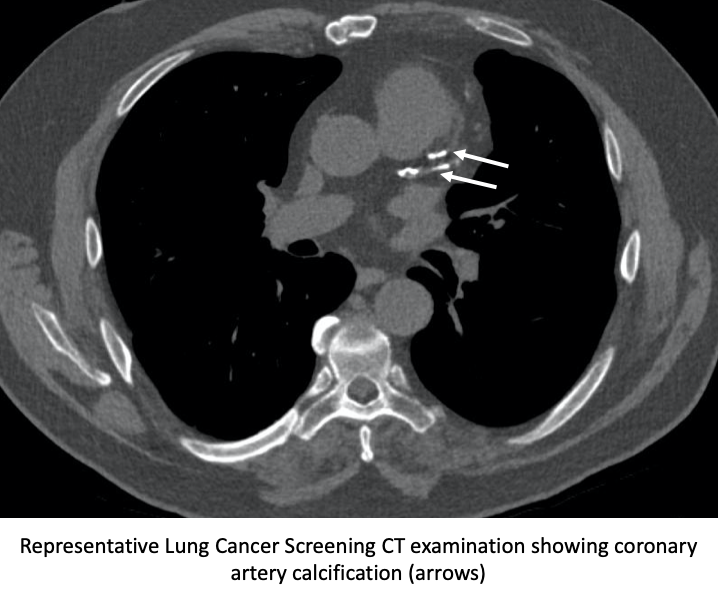

For people who are at high risk for lung cancer— particularly individuals with a longtime smoking history—annual screenings are essential.